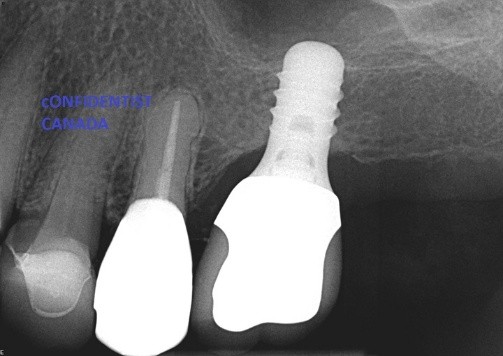

Regarding dental implant at site 3.6, there is evidence of